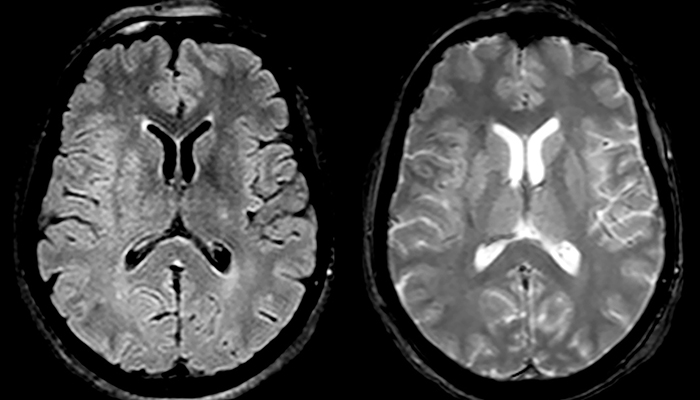

„Ingenia 3.0T liefert uns eine sehr gute Bildqualität mit hohem Signal-Rausch-Verhältnis, auch wenn wir die Auflösung ausreizen. Bei FLAIR-Bildern haben wir zum Beispiel eine isotrope Auflösung von 0,9 mm. Ingenia ermöglicht uns die Nutzung von 3D-T1-TSE mit BrainView, was eine bessere Empfindlichkeit als die 2D-Spinecho-Bildgebung[2] und die 3D-Gradientenecho-Bildgebung aufweist. Ingenia liefert auch hoch reproduzierbare Untersuchungen, was bei der MS-Bildgebung wichtig ist, damit Folgeuntersuchungen zu verschiedenen Zeitpunkten auf dieselbe Weise durchgeführt werden.“

Für die MS-Bildgebung im Gehirn nutzt Dr. Savatovsky 3D-FLAIR als Basissequenz, um die Läsionen darzustellen sowie die jeweilige Situation und die Läsionsbelastung zu beurteilen. „Wir zählen die Läsionen an jeder Stelle, um zu bestimmen, ob die Kriterien der Erkrankung erfüllt sind. Dafür wird eine T2-gewichtete Sequenz verwendet, weil unsere Neurologen diese gewohnt sind. Wir vergleichen die Läsionsbelastung unter FLAIR mit einer 3D-T1-Postkontrastsequenz, damit wir feststellen können, ob die Läsionen alt oder neu sind. In der Regel verabreichen wir das Kontrastmittel vor der Aufnahme des Patienten in das System, weil sich dadurch die Untersuchungsdauer verkürzt und die Visualisierung aktiver Läsionen möglich wird, die im Allgemeinen nach mehreren Minuten deutlicher dargestellt werden. Wenn sich eine differenzielle Diagnose als schwierig herausstellt, nutzen wir weitere Sequenzen wie die Suszeptibilitätsbildgebung, da einige fokale MS-Läsionen in der Mitte eine kleine Ader aufweisen[3].“

„In Frankreich werden Schlaganfälle in der Regel per MRT und nicht per CT untersucht, auch bei der Notfallbehandlung.“ „In Frankreich erfolgt die Bildgebung bei Schlaganfällen in der Regel per MRT, nicht per CT, auch bei der Notfallbehandlung. Das liegt daran, dass wir mit der MRT eine Ischämie in der akuten Phase direkt darstellen, aber auch Differenzialdiagnosen wie MS und Hämatom ausschließen können. Außerdem ist es uns möglich, die intrakraniellen und extrakraniellen Gefäße im Laufe derselben Untersuchung zu beurteilen“, sagt Dr. Savatovsky.

„Ingenia bietet eine große Flexibilität bei der Parametereinstellung, d.h., wir können eine Sequenz beliebig abstimmen“, erklärt Dr. Savatovsky. „Bei einer Schlaganfalluntersuchung nutzen wir zum Beispiel eine FLAIR-Sequenz von etwa zwei Minuten anstelle der vierminütigen Sequenz, die wir bei MS verwenden. Die Diffusionsbildgebung dauert 30 Sekunden, der T2*-gewichtete Scan ebenfalls 30 Sekunden und die Scan-Dauer bei der Angiographie beträgt weniger als eine Minute. Ingenia ist in dieser Situation ein großartiger Scanner. Auch bei diesen schnellen Sequenzen erzielen wir hochwertige Bilder mit einem guten Signal-Rausch-Verhältnis. Wenn wir anhand der ersten Sequenz feststellen, dass es sich nicht um einen ischämischen Schlaganfall, sondern um einen hämorrhagischen Schlaganfall handelt, können wir zu einer zeitaufgelösten Angiographie wechseln, um nach vaskulären Malformationen und einer Venenthrombose zu suchen.“

„Jede Klinik arbeitet anders, aber für mich umfasst das ideale Schlaganfallprotokoll die diffusionsgewichtete Bildgebung, die FLAIR- und die schnelle suszeptibilitätsgewichtete Bildgebung“, sagt Dr. Savatovsky. „Unsere schnelle suszeptibilitätsgewichtete Bildgebung dauert nur 50 Sekunden, sie ist also genauso schnell wie die T2*-gewichtete Bildgebung. Damit werden Blutungen, aber auch Koagulationen dargestellt. Wir führen zusätzlich eine 3D-MR-Angiographie durch, die Informationen über zervikale und zerebrale Gefäße liefert. Wenn die Patienten keine sofortige Behandlung benötigen oder wenn zusätzliche Informationen erforderlich sind, um über die Therapie zu entscheiden, nehmen wir außerdem eine Perfusionsbildgebung und eine T1-gewichtete Postkontrastbildgebung vor.“